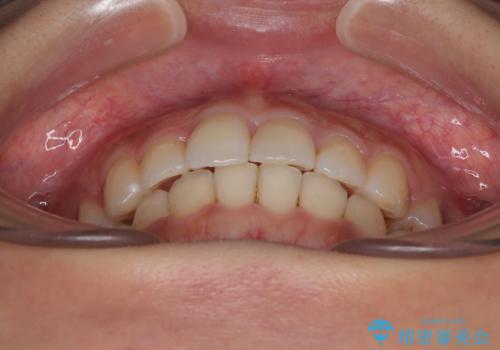

- 前歯のクロスバイトと口元の膨らんだ横顔の印象を気にして来院された患者様です。

ご本人の気にされている口元は、分析数値からするとそれほど突出しているものではありませんでした。

しかしながら。そのまま叢生を解消すると横顔が突出した印象になる可能性が高かったため、上下左右の小臼歯4本を抜歯して、ワイヤー装置にて矯正治療を行うこととしました。

上下左右の第一小臼歯4本を抜歯して治療を行うことがセオリーでしたが、左下は第二小臼歯が銀歯であったため、イレギュラーではありますが、そちらを抜歯しました。

その影響で治療期間は長くなりましたが、処置していない歯を保存することができました。